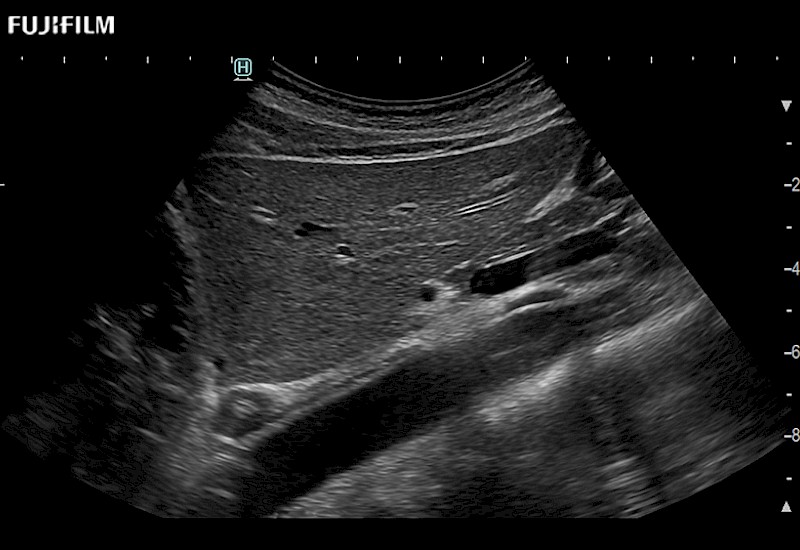

for use during open and laparoscopic procedures: Tumor localization & staging, Ablation, Resection, Biopsy, Transplant, Abdominal exploration, Robotic surgery

The ARIETTA 750 incorporates all of the proven technologies and functions that medical professionals have come to expect from Fujifilm Healthcare.

ARIETTA 750 is the definitive diagnostic ultrasound solution for any clinical setting - Private Office, Imaging Center, or Hospital. The ARIETTA platform provides the ultimate in clinical performance with its state-of-the-art features and large user-friendly display.

The ARIETTA 650 DI combines trusted Fujifilm Healthcare technologies and features tailored for surgical oncology.

Designed to meet the demands of surgeons, the ARIETTA 650 DI offers precise guidance. Its advanced capabilities and large, intuitive display offer accurate and efficient care in operating rooms and specialized surgical settings.